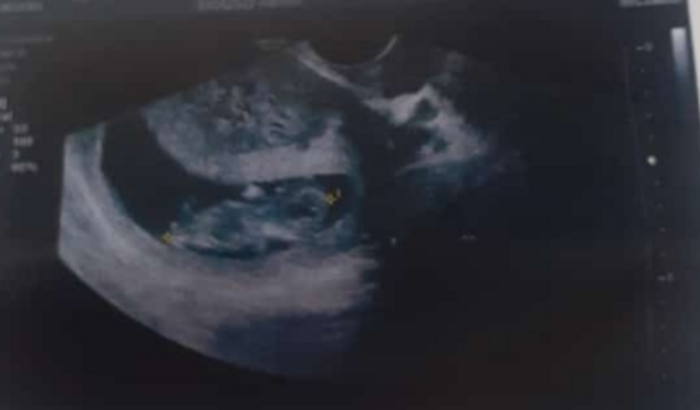

Eu tenho 35anos uma filha de 17anos por motivo de fazer tratamento em uma ferida no ulturo parei de tomar o anticoncepcional e engravidei estou em desespero pois estou com diabete gestacional e na categoria de obesa. Hospital público infelizmente é complicado meu sonho no momento é ter meu bebê no particular pesquisei e fica em torno de 12mil.